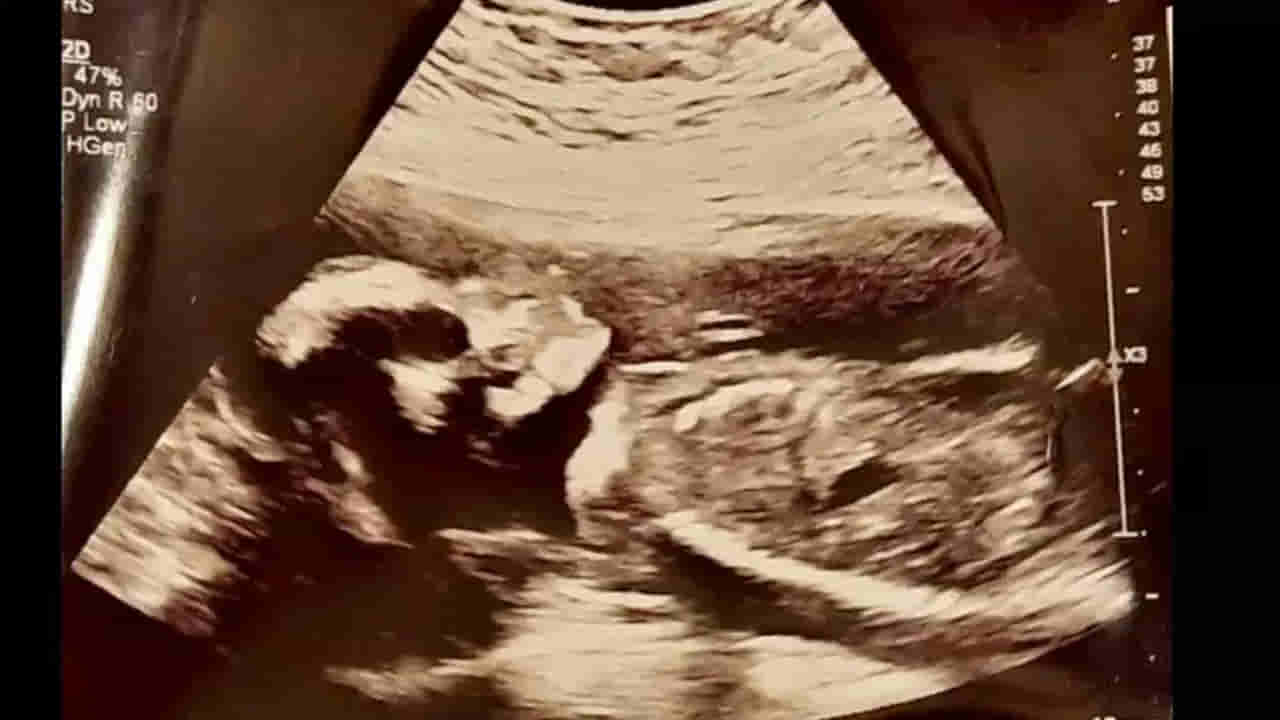

వివరాల్లోకి వెళ్తే.. స్కాట్లాండ్లోని డన్ఫెర్మ్లైన్కు చెందిన 25 ఏళ్ల తస్మిన్ స్టెన్హౌస్ ఐదు నెలల గర్భవతిగా ఉన్నప్పుడు పరీక్షల నిమిత్తం ఆస్పత్రికి వెళ్లగా.. అల్ట్రాసౌండ్ స్కాన్ ద్వారా తనకు పుట్టబోయే బిడ్డ ఎలా ఉందో చూడాలని అనుకుంది. ఆనందంగా ఆ స్కాన్ చేయించుకుంది. ఇక ఆ స్కాన్కు సంబంధించిన బ్లాక్ అండ్ వైట్ ఇమేజ్ను స్క్రీన్పై చూడగానే దెబ్బకు షాక్ అయింది. ఆ ఫోటోలో శిశువు తల పుర్రెను పోలి ఉండటాన్ని చూసి సదరు మహిళకు మైండ్ బ్లాంకయింది. ఆ తర్వాత తనకు జరిగిన ఈ అనుభవాన్ని తస్మిన్ తన భర్తతో పంచుకుంది. అతడి దానికి పగలబడి నవ్వాడు. దీన్ని సోషల్ మీడియా ద్వారా నెటిజన్లతో పంచుకుంది తస్మిన్. కాగా, తస్మిన్ 2022 ఫిబ్రవరిలో పండింటి ఆడబిడ్డకు జన్మనిచ్చింది. ఇక ఆ అమ్మాయి ముఖం ఎంతో అందంగా ఉందని.. తస్కిన్ స్వయంగా ప్రకటించింది.